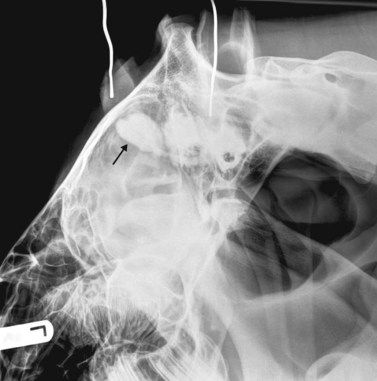

image

(B) Intra-oral radiograph taken intra-operatively during a dental extraction procedure. A small bone-opacity fragment can be seen in the rostral aspect of the alveolus (arrow).

(Radiograph courtesy of W.H. Tremaine.)